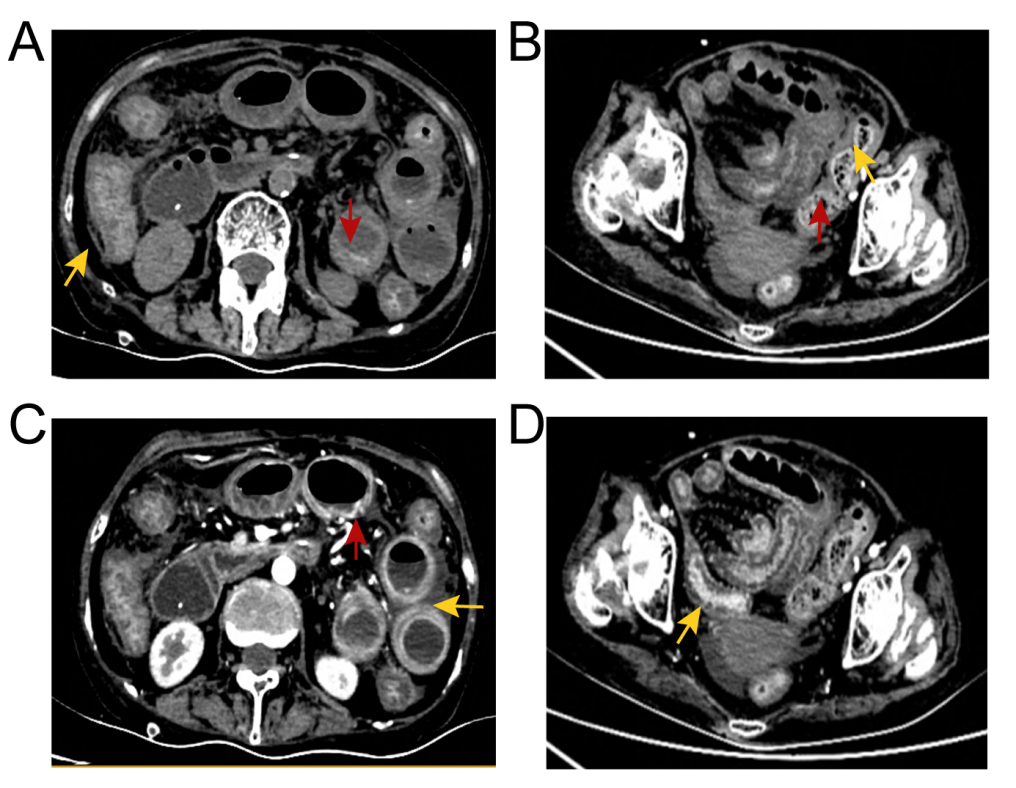

你听说过小肠结石肠梗阻吗

图片尺寸3968x2976